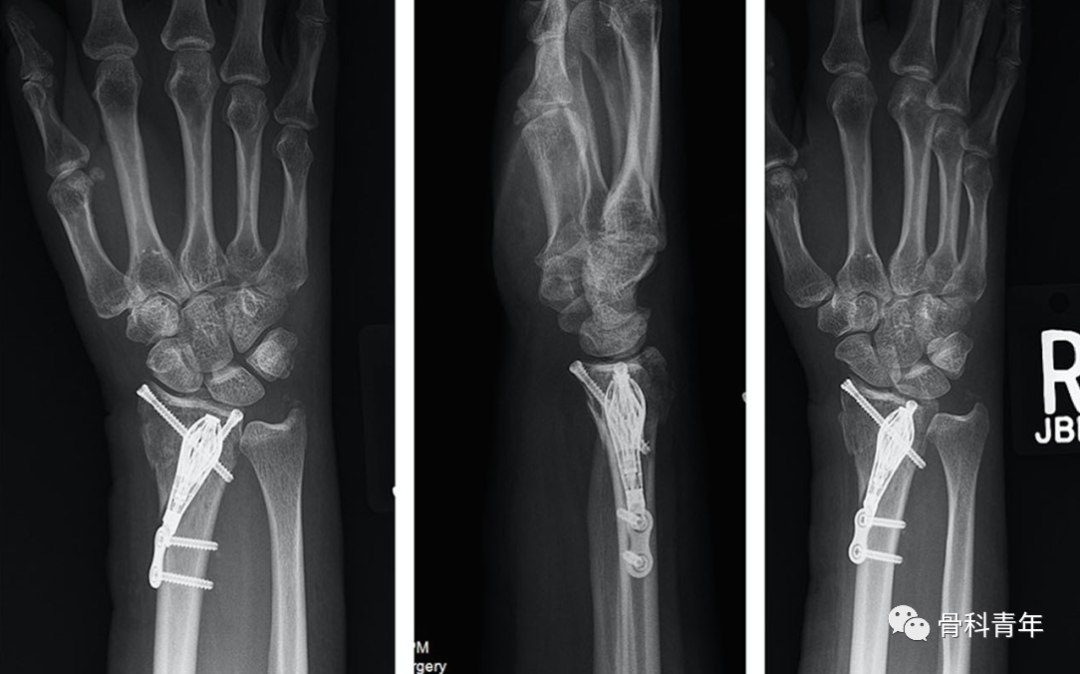

掌侧锁定加压接骨板(Volar locking compression plate,LCP)内固定是桡骨远端骨折治疗的金标准,但LCP并非对所有桡骨远端骨折均实用,如桡骨极远端骨折、背侧缘骨折、掌侧die-punch骨折等;同时,LCP钢板也存在较多的并发症,包括旋前方肌损伤、骨折血运破坏、掌侧软组织激惹、背侧肌腱磨损等,同时对严重骨质疏松患者存在较高的内固定失效风险。

对降低术后并发症和减少医源性损伤的需求,催生了各种新型内固定方式的发展。本文简要介绍4种新型内固定方式,供临床医生参考。